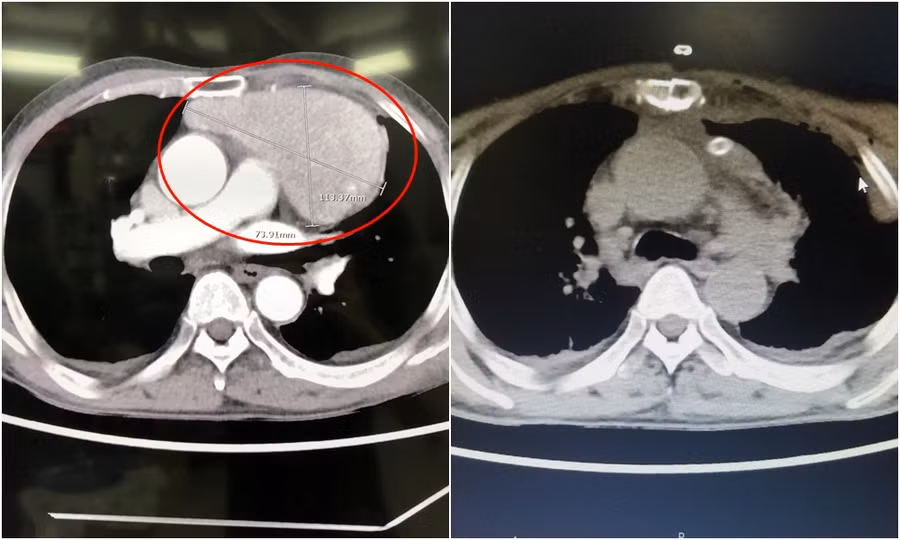

Sau khi thăm khám, các bác sĩ cho biết, khối u nằm ngay vùng trước tim, kích thước lớn bằng quả tim bệnh nhân, đè đẩy các mạch máu, tim và khí phế quản.

Các bác sĩ tiến hành phẫu thuật theo đường mở xương ức và ngực trái, lộ khối u trung thất lớn kích thước 11x7x7cm nằm đè lên tim và ép các mạch máu về tim, u tăng sinh nhiều mạch lớn dính vào các tổ chức xung quanh.

Sau hơn 2 giờ phẫu thuật, các bác sĩ đã bóc tách, lấy trọn khối u và tổ chức xung quanh, bảo tồn nguyên vẹn tim và các mạch máu thần kinh quan trọng vùng tim. Hiện tại, tình trạng sức khoẻ bệnh nhân ổn định, đỡ đau tức ngực, có thể ăn uống và vận động nhẹ nhàng.